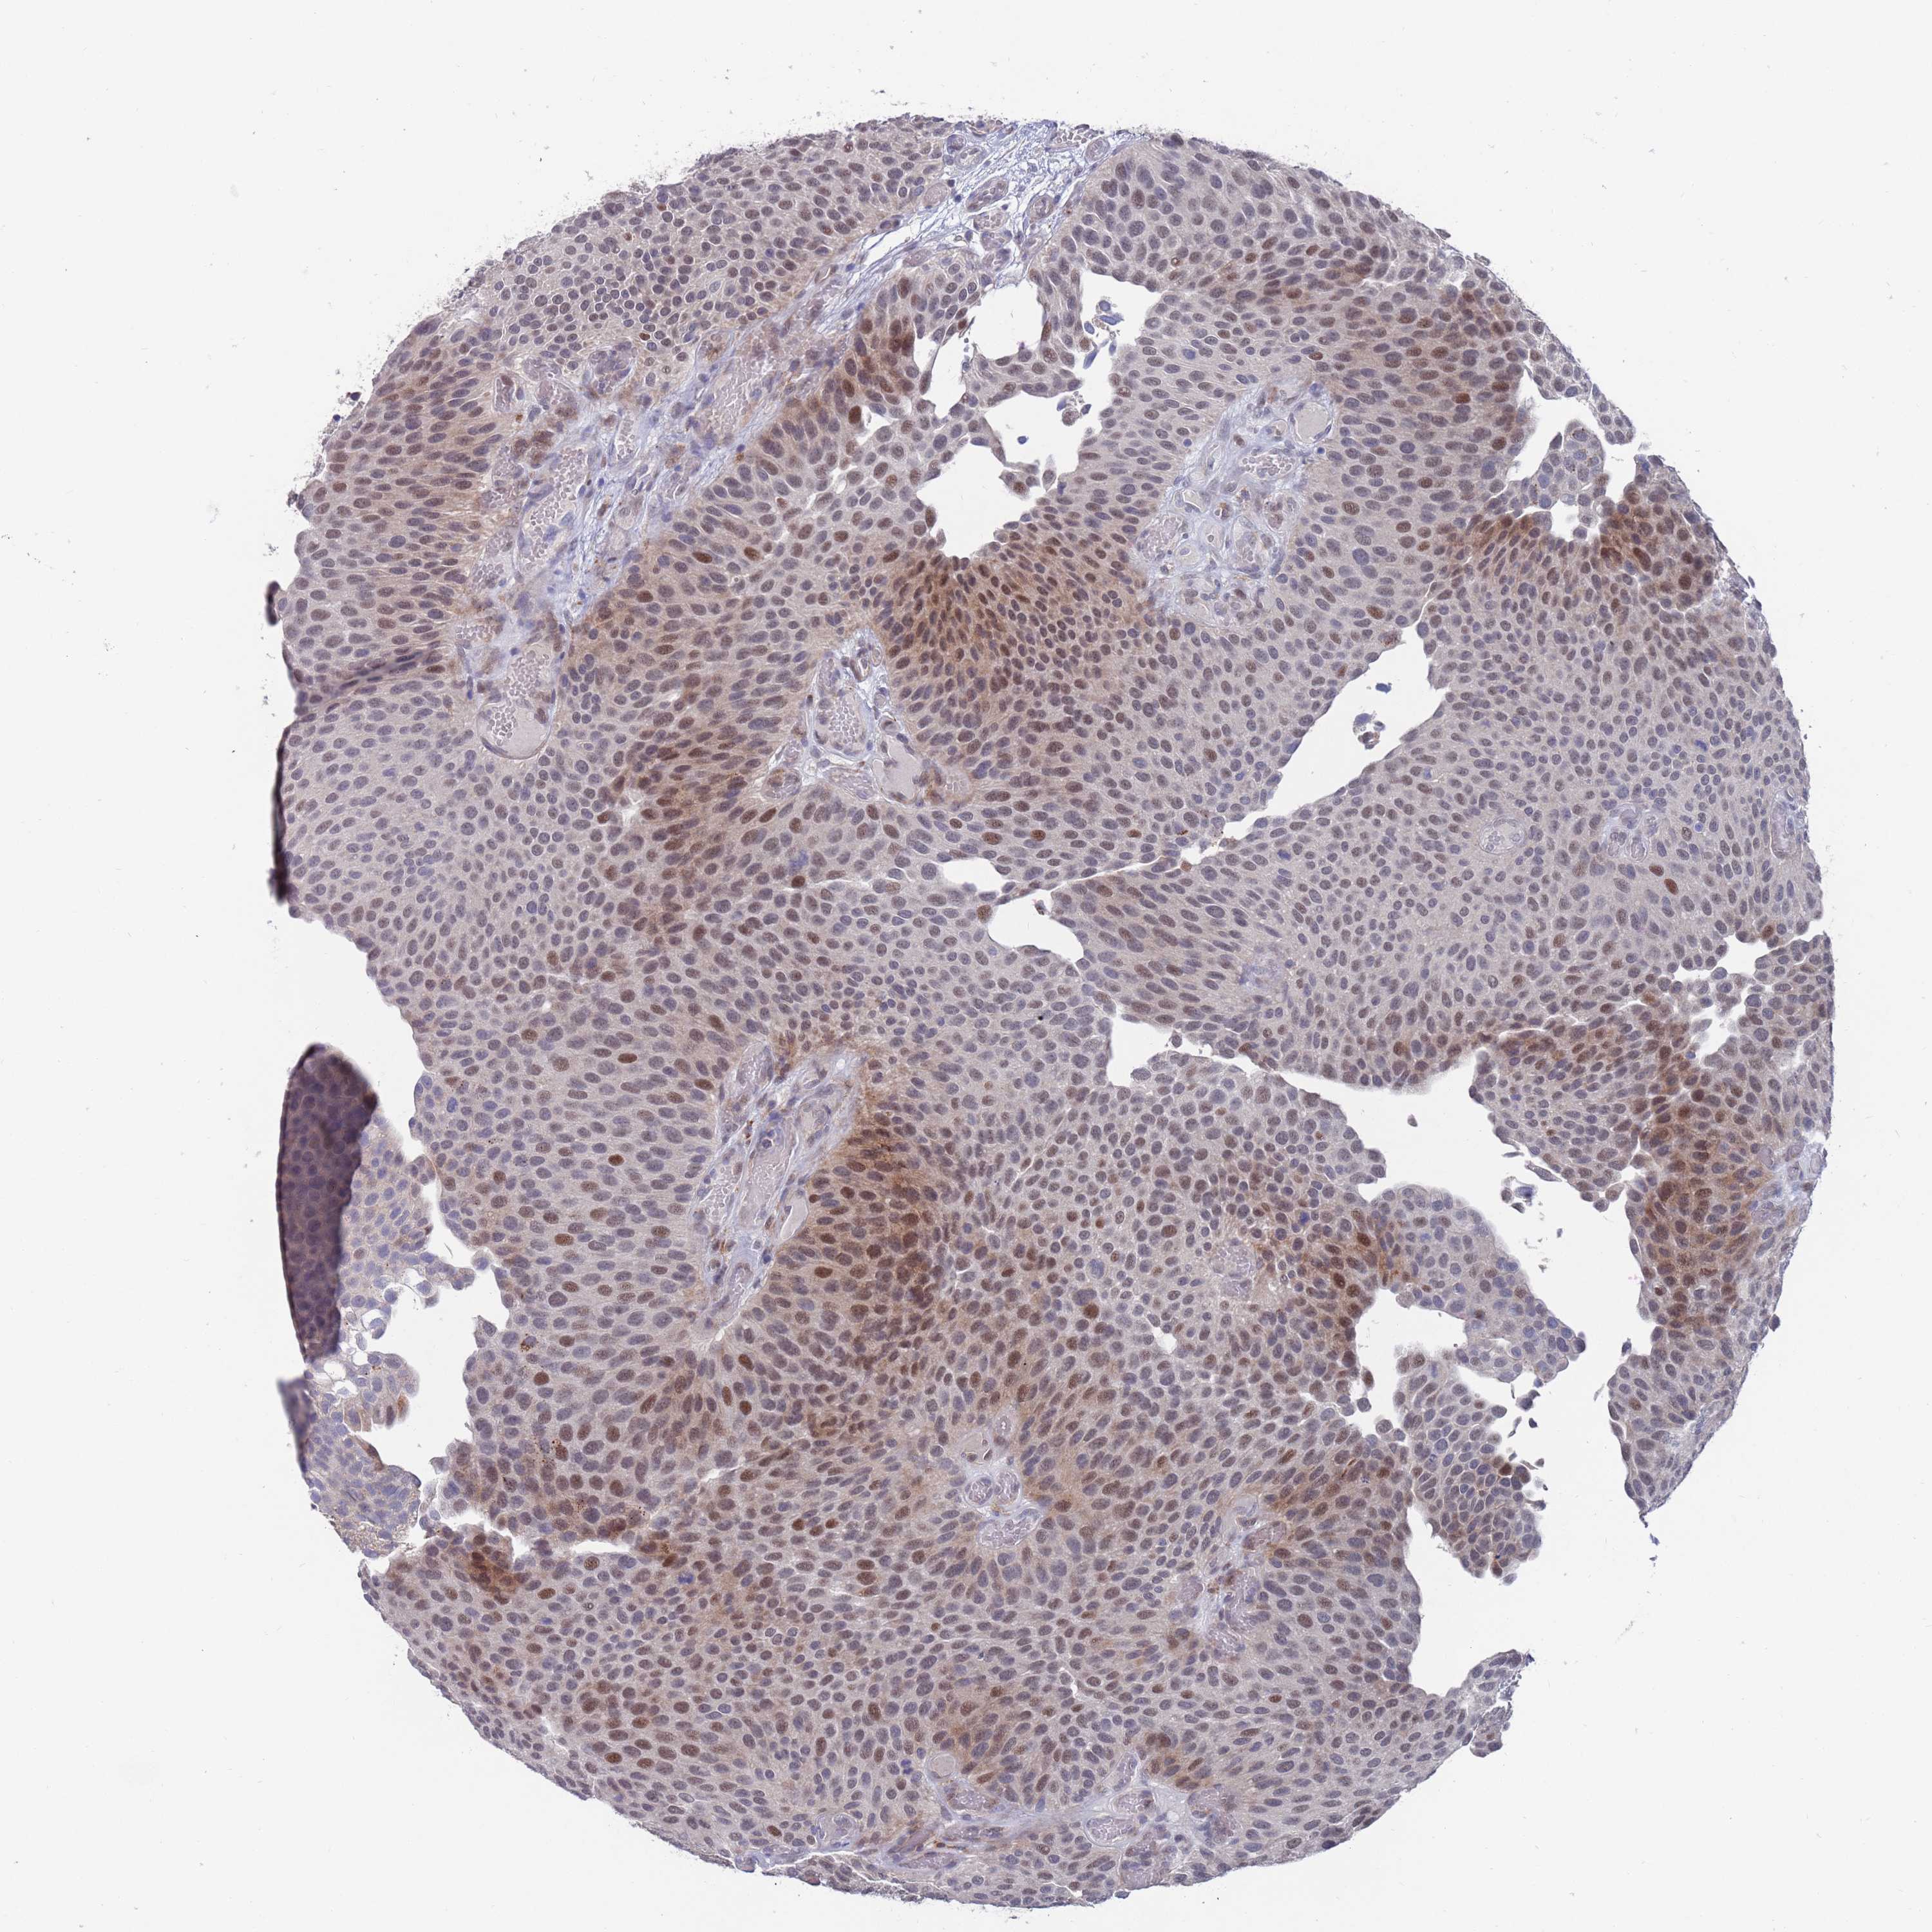

UROTHELIAL CANCER - Protein expressioni

A mouse-over function shows sample information and annotation data. Click on an image to view it in a full screen mode. Samples can be filtered based on level of antibody staining by selecting one or several of the following categories: high, medium, low and not detected. The assay and annotation is described here.

Note that samples used for immunohistochemistry by the Human Protein Atlas do not correspond to samples in the TCGA dataset.

Antibody stainingi

Antibody staining in the annotated cell types in the current human tissue is reported as not detected, low, medium, or high, based on conventional immunohistochemistry profiling in selected tissues. This score is based on the combination of the staining intensity and fraction of stained cells.

Each image is clickable and will lead to virtual microscopy that enables deeper exploration of all samples and also displays staining intensity scores, fraction scores and subcellular localization as well as patient and tissue information for each sample.

Antibody HPA046800

Staining

High

Medium

Low

Not detected

Intensity

Strong

Moderate

Weak

Negative

Quantity

>75%

75%-25%

<25%

None

Location

Nuclear

Cytoplasmic/membranous

Cytoplasmic/membranous,nuclear

Urothelial carcinoma, High grade

Urothelial carcinoma, Low grade